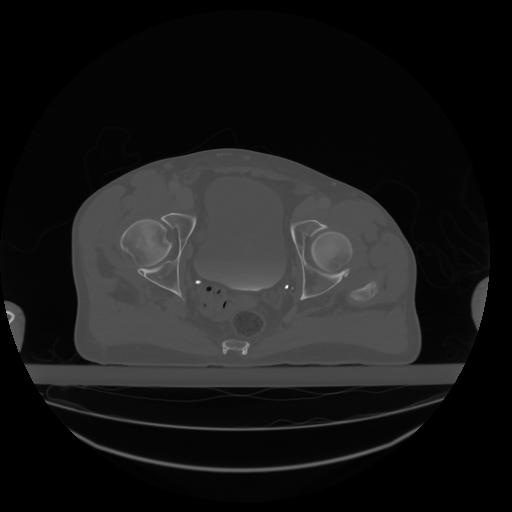

27 CUERPO,CE,Axial,3.0,CUERPO,,